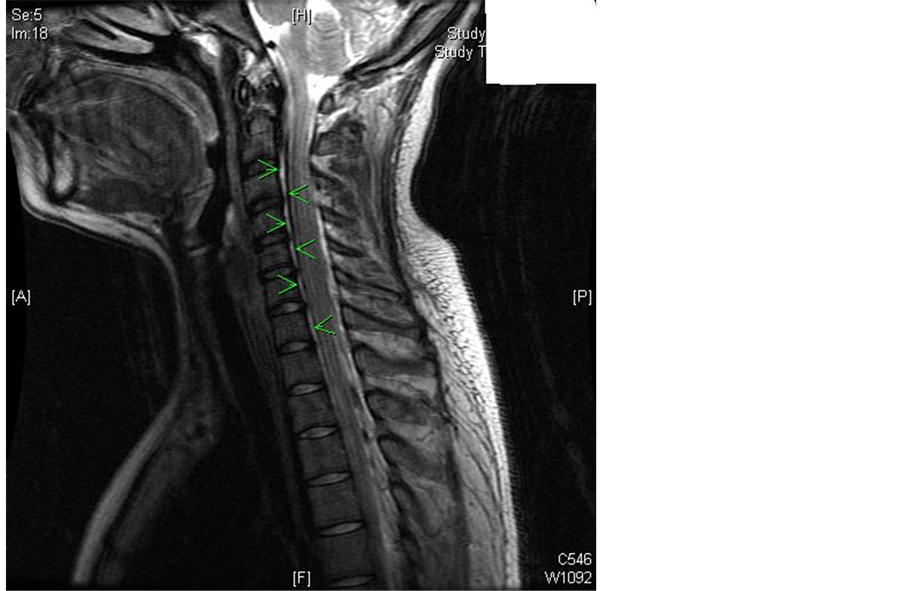

Twelve hours post delivery the patient began to complain of headache and neck pain, described as 6/10 in intensity, and only mildly increased in the upright position. The neck pain improved with bed rest, hydration and analgesics. However, approximately twenty four hours later, the patient reported an acute worsening of her neck pain when she attempted ambulation to the shower. Due to the somewhat unusual presentation of symptoms and elevated patient concern, an MRI of the brain and neck was obtained (Figure 1).

Magnetic resonance imaging in this case showed the presence of a dark epidural collection (indicated by green arrows), possibly fluid, partially collapsing the thecal sac from C2-3 through the lowest level of the included cervical spine, with some persistent fluid surrounding the cord. This was thought to indicate dilated epidural veins relating to spontaneous intracranial hypotension or alternatively, epidural fluid.

Figure 1. Dark epidural collection, indicated by green arrows. (IMAGE AS SEPARATE FILE).